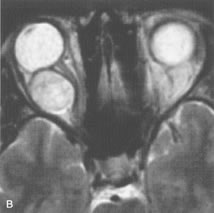

Metastatic Tumors

Breast carcinoma metastatic to the orbit has been demonstrated to be hypointense to the surrounding orbital fat on T1-weighted studies and hyperintense on T2-weighted images and has an affinity to the extraocular muscles (Fig. 20).50,64 The MRI characteristics of prostate carcinoma metastatic to the orbit have been described as involving the greater and lesser wing of the sphenoid, orbital roof, and optic canal. Diffuse bone hypertrophy with isointense or slightly hyperintense tissue on T1-weighted images represents the osteoblastic carcinomatous bone infiltration. Contrast enhancement is variable on T1-weighted and fat-suppressed images.65

Fig. 20. A. T1-weighted MR scan demonstrates nodular enlargement of both medial rectus muscles (arrows). B. T1-weighted fat-suppressed contrast-enhanced scan confirms the presence of small metnstatic deposits within the muscles (open arrows).

Most other metastatic tumors also have a lower intensity signal on T1-weighted images and appear to displace or infiltrate normal orbital structures; however, their signal characteristics are variable on T2-weighted MR images.66 Many metastatic tumors demonstrate bright contrast enhancement with Gd-DTPA.